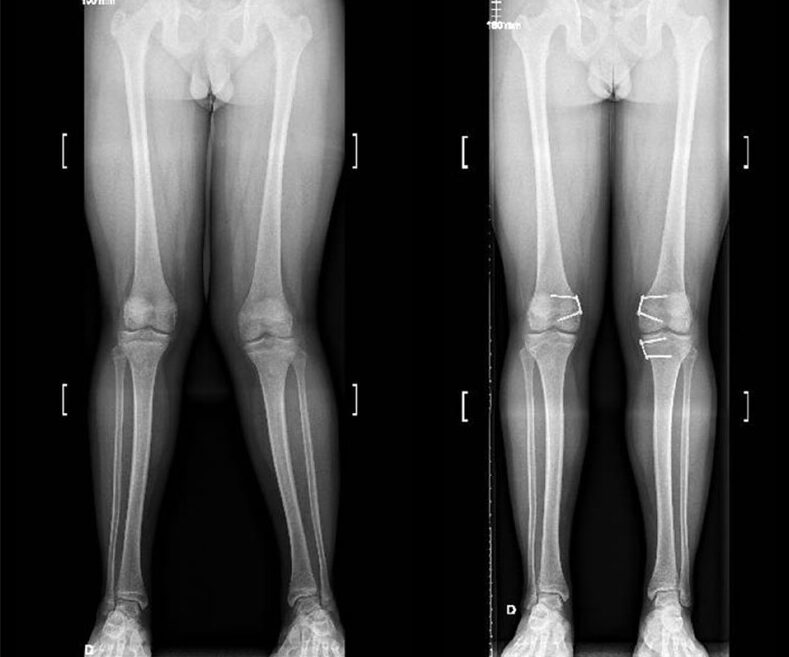

پای پرانتزی (Genu Varum) یا واروس یک ناهنجاری ساختاری در پاهاست که در آن زانوها به هم نزدیک نمیشوند و پاها به شکل پرانتزی از هم فاصله دارند. این وضعیت ممکن است ناشی از مشکلات ژنتیکی، رشد ناهنجار استخوانها، یا عوامل دیگری مانند عادات نادرست حرکتی و قرارگیری نادرست پاها در طول دوران رشد باشد.

پای پرانتزی میتواند منجر به افزایش فشار بر روی بخش داخلی زانو شود و احتمال بروز آرتروز زانو را افزایش دهد. در این حالت، به دلیل انحنای غیرطبیعی پا، تراز بدن تغییر میکند و فشار به طور نامتقارن روی زانوها وارد میشود.

افرادی که دارای پای پرانتزی هستند به دلیل انحراف در زاویه پا، فشار بیشتری را بر روی بخش داخلی زانو تحمل میکنند. این فشار اضافی میتواند باعث تحلیل رفتن سریعتر غضروف در قسمت داخلی زانو و در نهایت بروز آرتروز زانو شود.

در حالت عادی، فشار روی زانو به طور متعادل در سراسر مفصل توزیع میشود. اما در پای پرانتزی، وزن بدن بیشتر به بخش داخلی زانو منتقل میشود و همین موضوع احتمال ایجاد آسیب و تحلیل غضروف را افزایش میدهد.

- رادیوگرافی: عکسبرداری با اشعه ایکس میتواند تغییرات غضروف، فشردگی فضای مفصل و زوایای غیرعادی زانو را نشان دهد.

استئوتومی زانو: در این روش، قسمتی از استخوان ساق پا یا ران به منظور تغییر زاویه زانو و توزیع بهتر فشار تراشیده میشود.